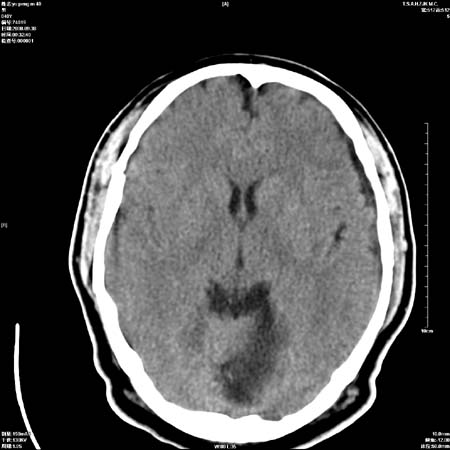

以下是引用流浪星在2008-10-4 20:06:00的发言:[br]大脑大静脉池增宽,脑萎缩引起,目前的ct表现不能解释临床症状,建议短期复查或做mr检查。